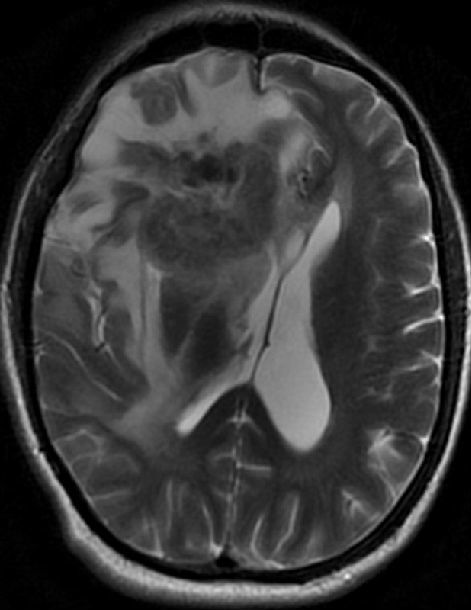

图 A:横断面 MRI T2 像显示右额叶可见一不均匀的病灶,病灶周围有血管性水肿。水肿压迫了同侧的侧脑室,中线向左偏移;